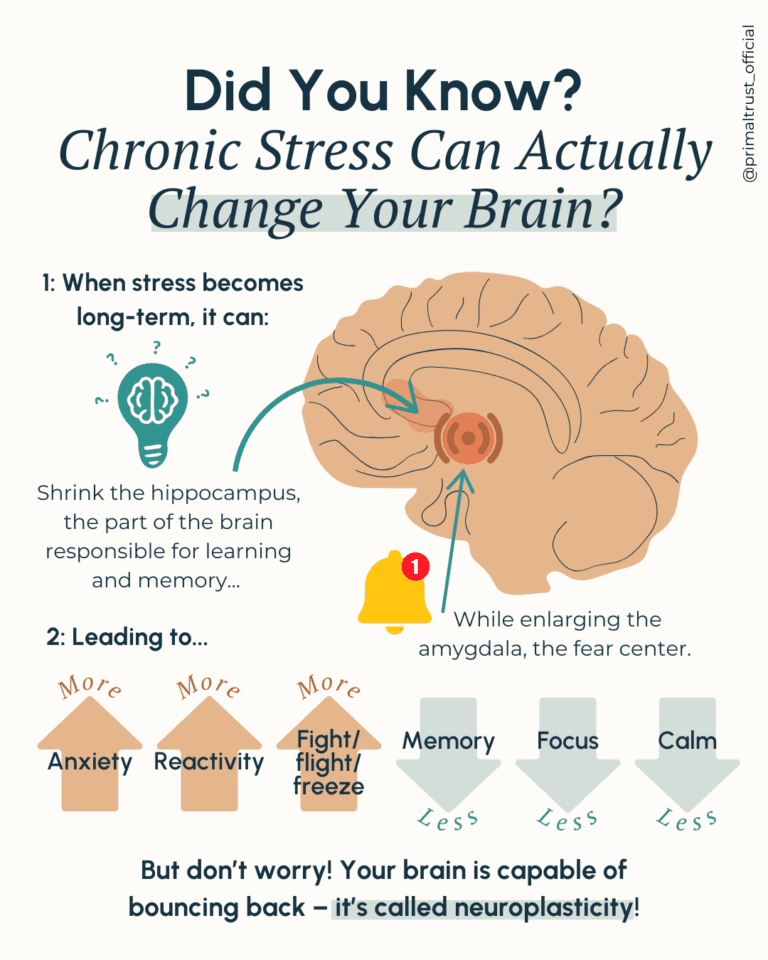

The Impact of Constant Stress on the Brain

Research suggests that chronic stress can cause changes in neural connections in various parts of the brain, including the hippocampus, prefrontal cortex, and amygdala. This shift can increase anxiety, cause memory loss and changes in learning and memory, and influences decision-making. These changes can be associated with a heightened state of alertness, designing a significant impact on daily routine.